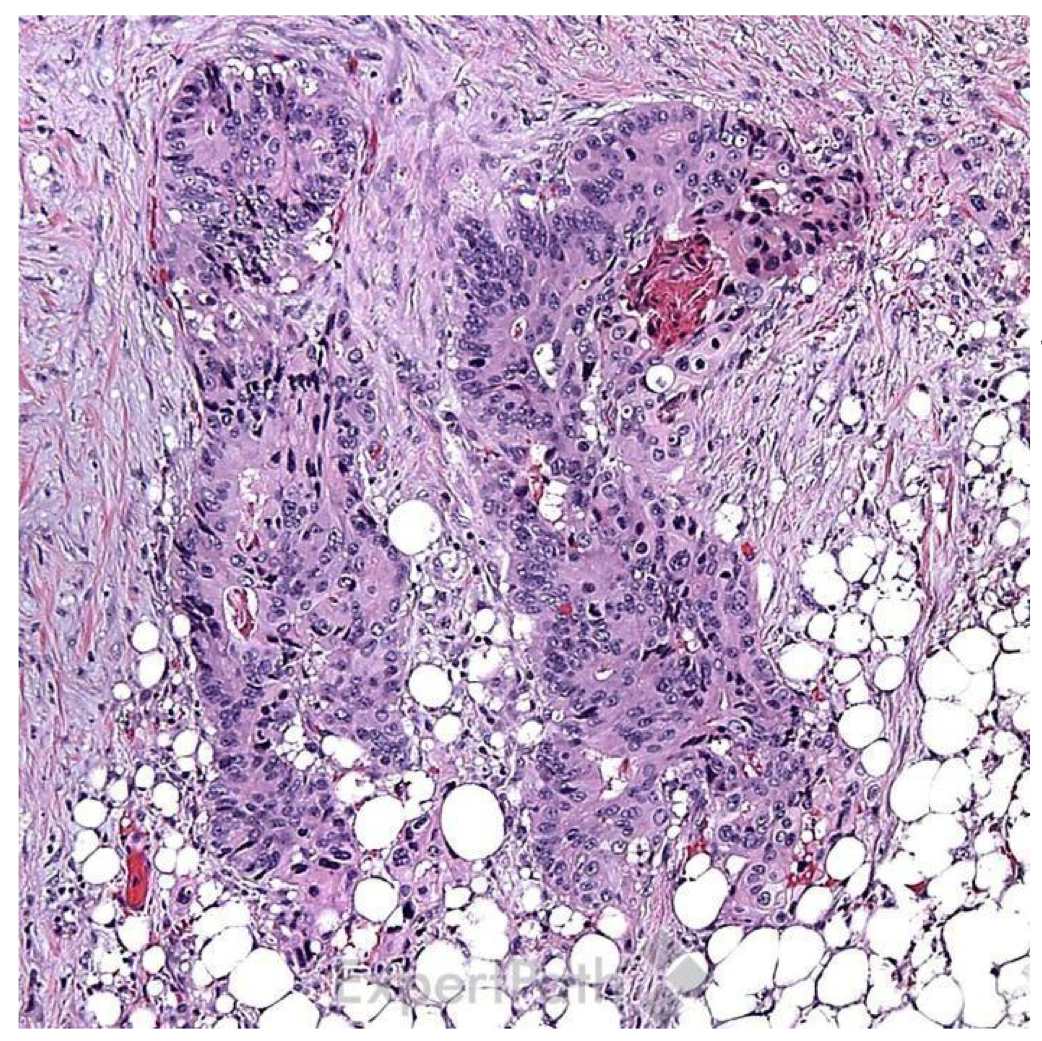

what is the diagnosis?

invasive colonic adenocarcinoma (forming glands)